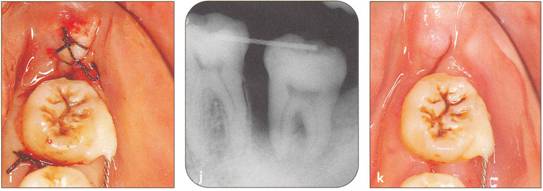

Fi 545e45f g 5-2j After suturing of the gingival flap and fixation of the donor tooth using sutures. |

Fi 545e45f g 5-2i The recipient site right before transplant procedure (2 weeks after extraction of the first molar). |

Fi 545e45f g 5-2k After transplantation. |